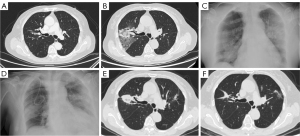

Pleural pain and pneumothorax were the most comment treatment-related complications that frequently occurred together. The patient in Figure 1 developed right-sided pleuritic pain. A chest X-ray at 3 days revealed a right-sided pneumothorax. The condition was managed conservatively with supplemental oxygen and antibiotics. The patient’s hospitalization was prolonged due to pneumothorax exacerbation, requiring thoracic closed drainage. A CT at 4 days revealed the disappearance of the right pneumothorax. Subsequent CT at 1 and 12 months revealed that the pulmonary solid shadow gradually became smaller. Additional representative cases (Figure S2) showed delayed pleural effusion and cavitation, both recovered after symptomatic treatment.